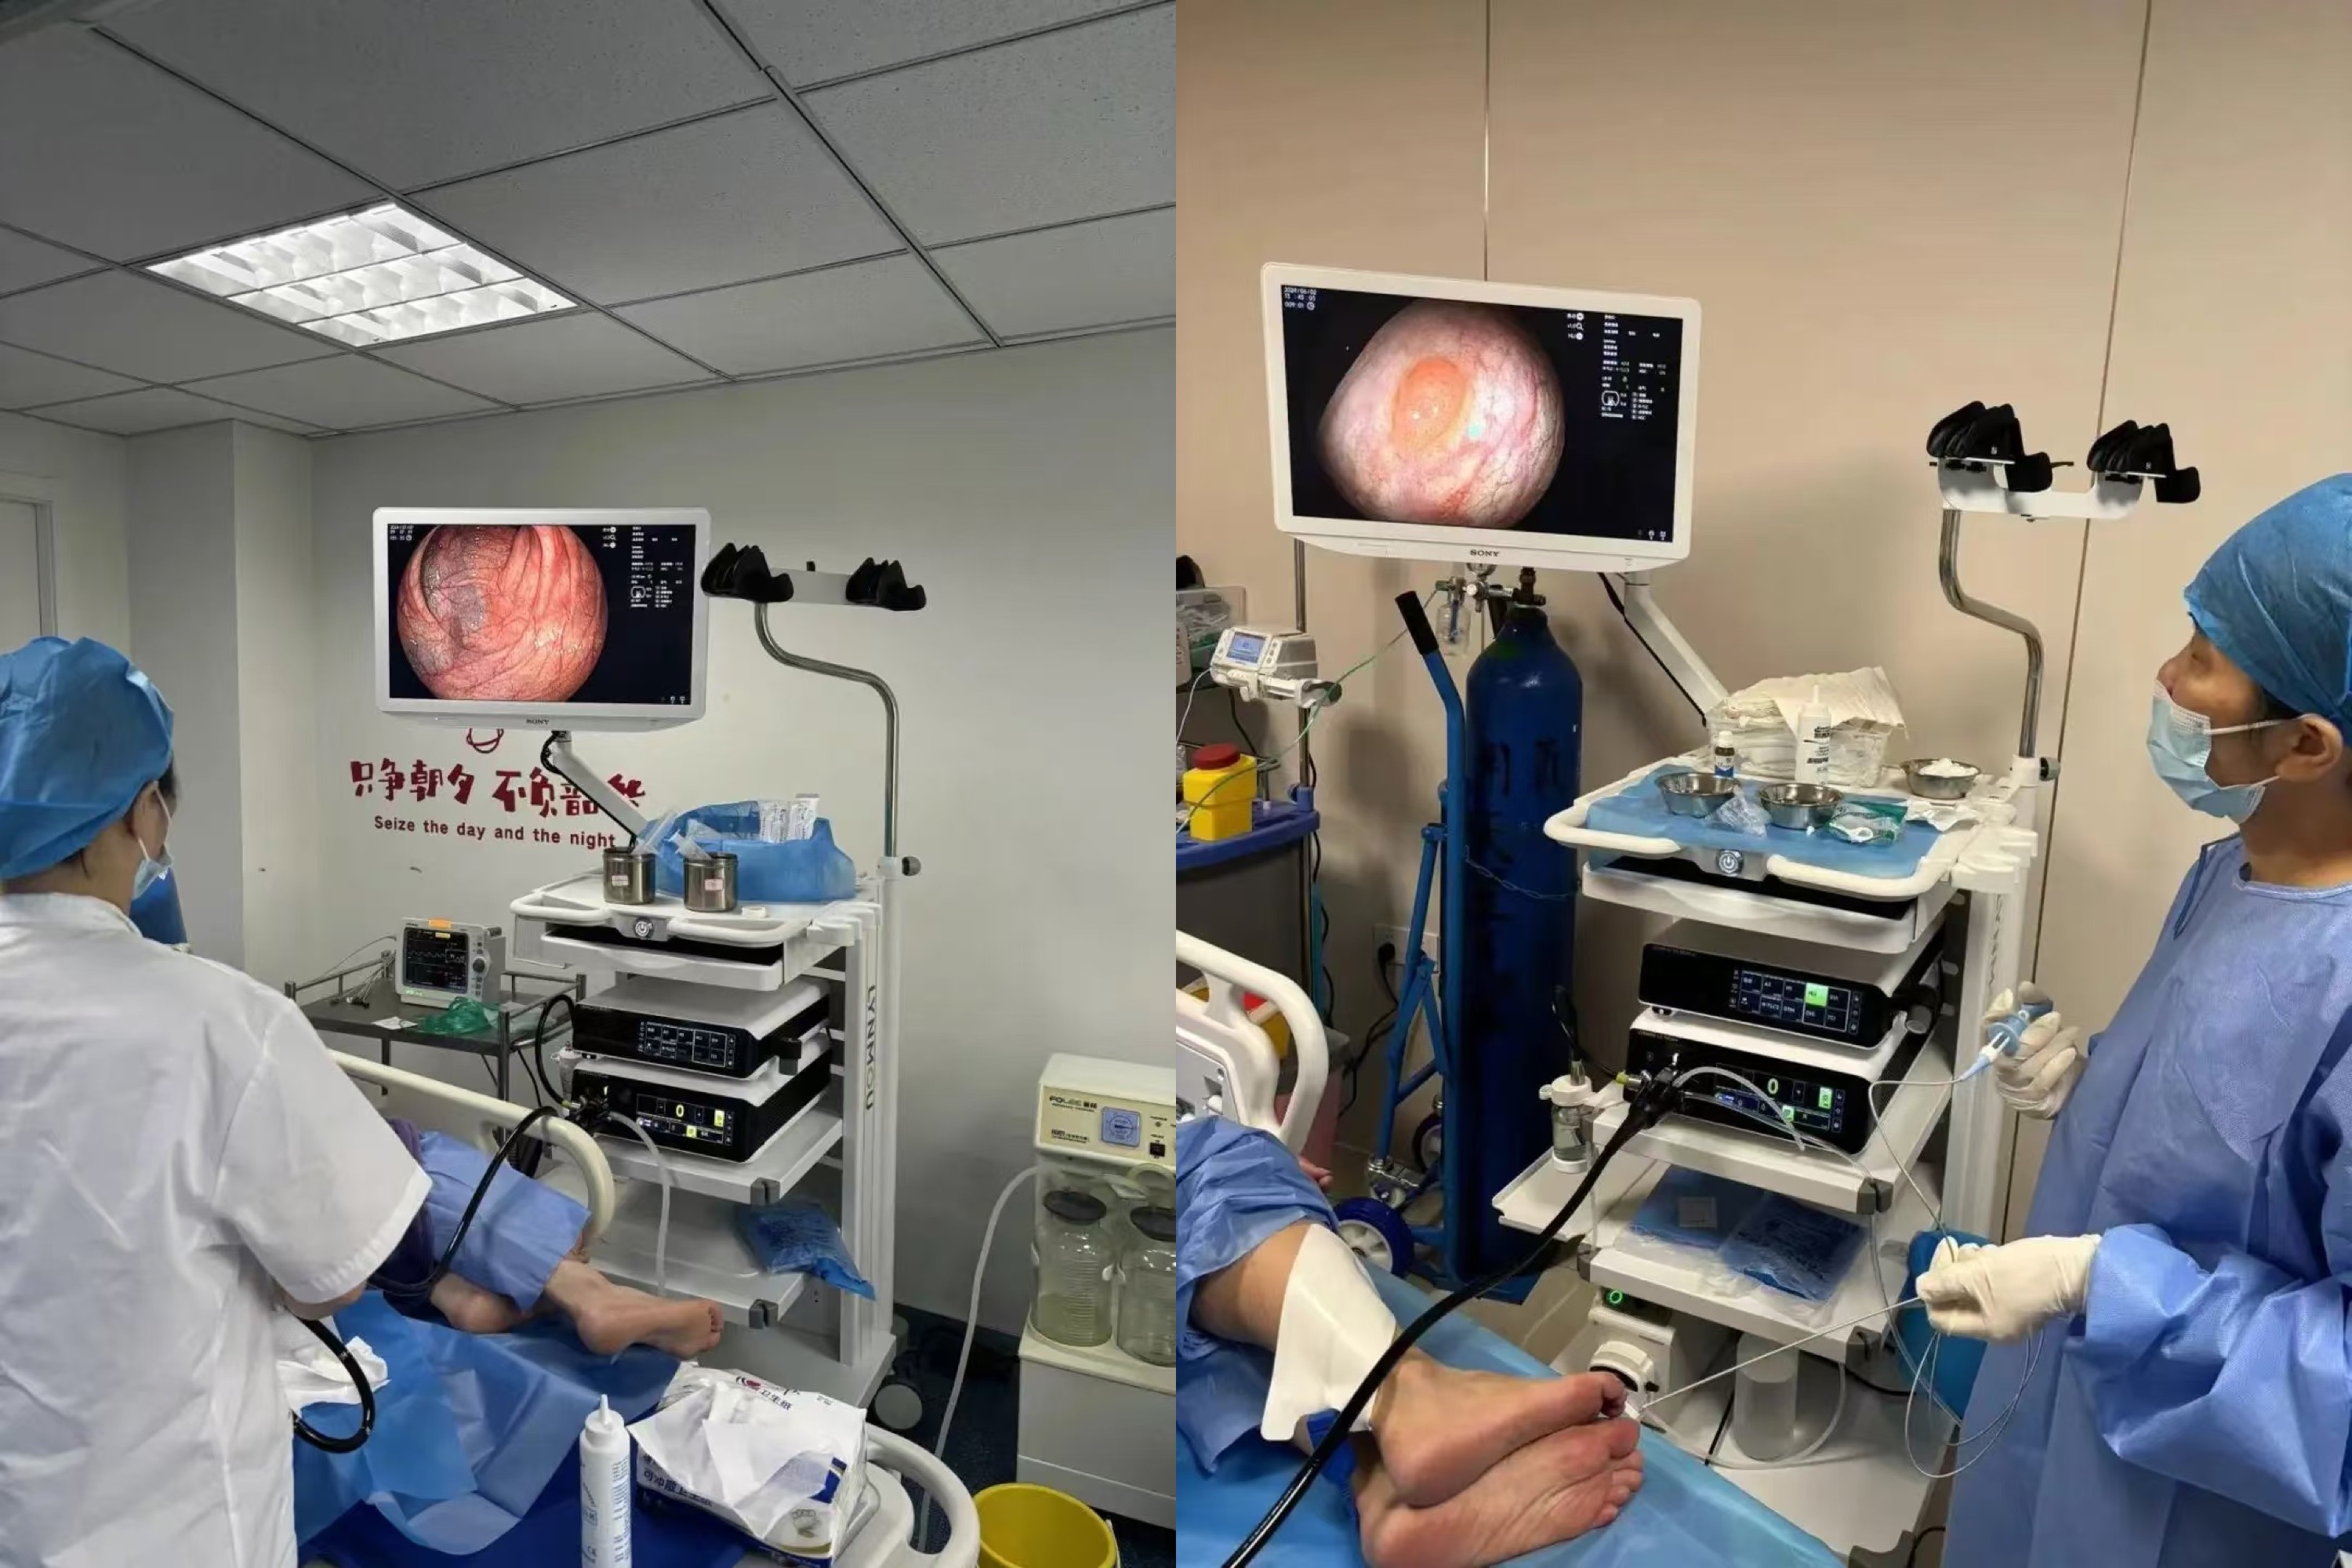

After installation, the hospital immediately arranged patients for clinical trials. The feedback results showed that Lynmou Endoscopy performs excellently in improving examination comfort, reducing examination time, and enhancing diagnostic accuracy. Its Full-Scenario imaging and excellent maneuverability effectively help achieve early screening, diagnosis and treatment.

Hospital director highly praised Lynmou Endoscopy, "Lynmou's products not only demonstrate the innovative strength of domestic medical devices with their excellent performance, but also bring unprecedented efficiency to primary hospitals in the diagnosis and treatment of gastrointestinal diseases. This greatly improves our level of diagnosis and treatment, providing patients with more timely and accurate medical services, while also offering strong technical support to doctors. This is fortunate for both patients and doctors."